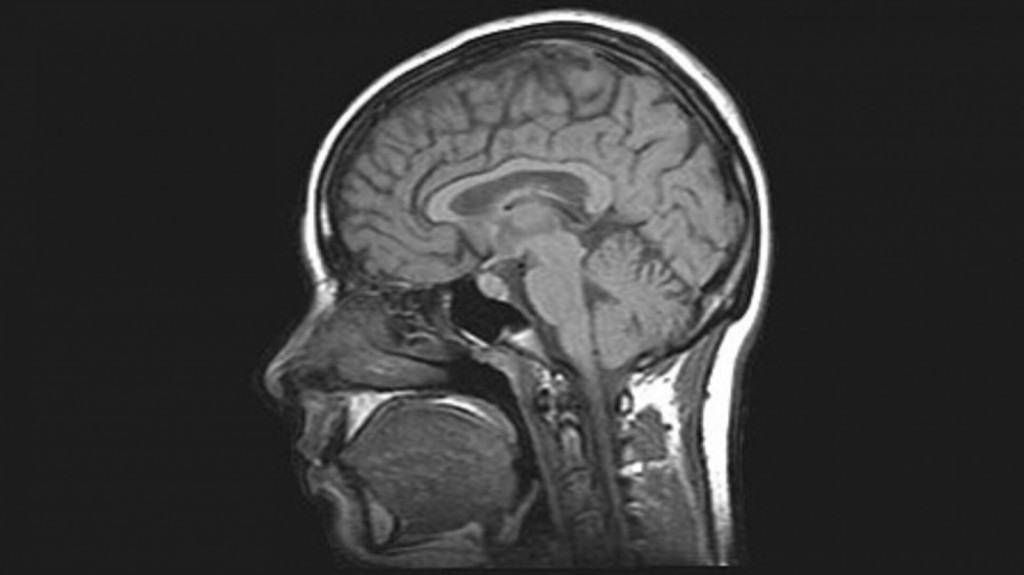

Μεταξύ σχεδόν 40.000 ασθενών που νοσηλεύτηκαν σε ΗΠΑ και Ευρώπη με κοροναϊό, περίπου το 11% θεωρήθηκε ύποπτο για επιπλοκές στον εγκέφαλο και υποβλήθηκε σε αξονική και μαγνητική τομογραφία.

Εγκεφαλικές αλλοιώσεις που πιθανότατα σχετίζονται με τον κοροναϊό ανιχνεύθηκαν στο 10% αυτών των ύποπτων κρουσμάτων, κάτι που σημαίνει ότι οι επιπλοκές αυτές αντιστοιχούν στο 1,2% του συνόλου των νοσηλευόμενων ασθενών.

Η συχνότερες επιπλοκές ήταν το ισχαιμικό εγκεφαλικό επεισόδιο λόγω θρόμβων (6,2%), ενδοκρανιακή αιμορραγία (3,7%) και εγκεφαλίτιδα, ή φλεγμονή του εγκεφάλου (0,47%).